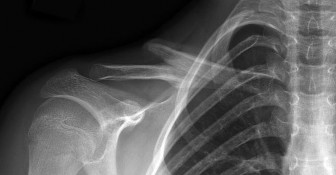

Question 38

A 9-year-old male presents with acute shoulder pain after throwing a baseball. Radiographs reveal a pathologic fracture through a centrally located, lytic, expansile bone lesion in the proximal humeral metaphysis. A "fallen leaf" sign is noted. What is the most appropriate initial management?